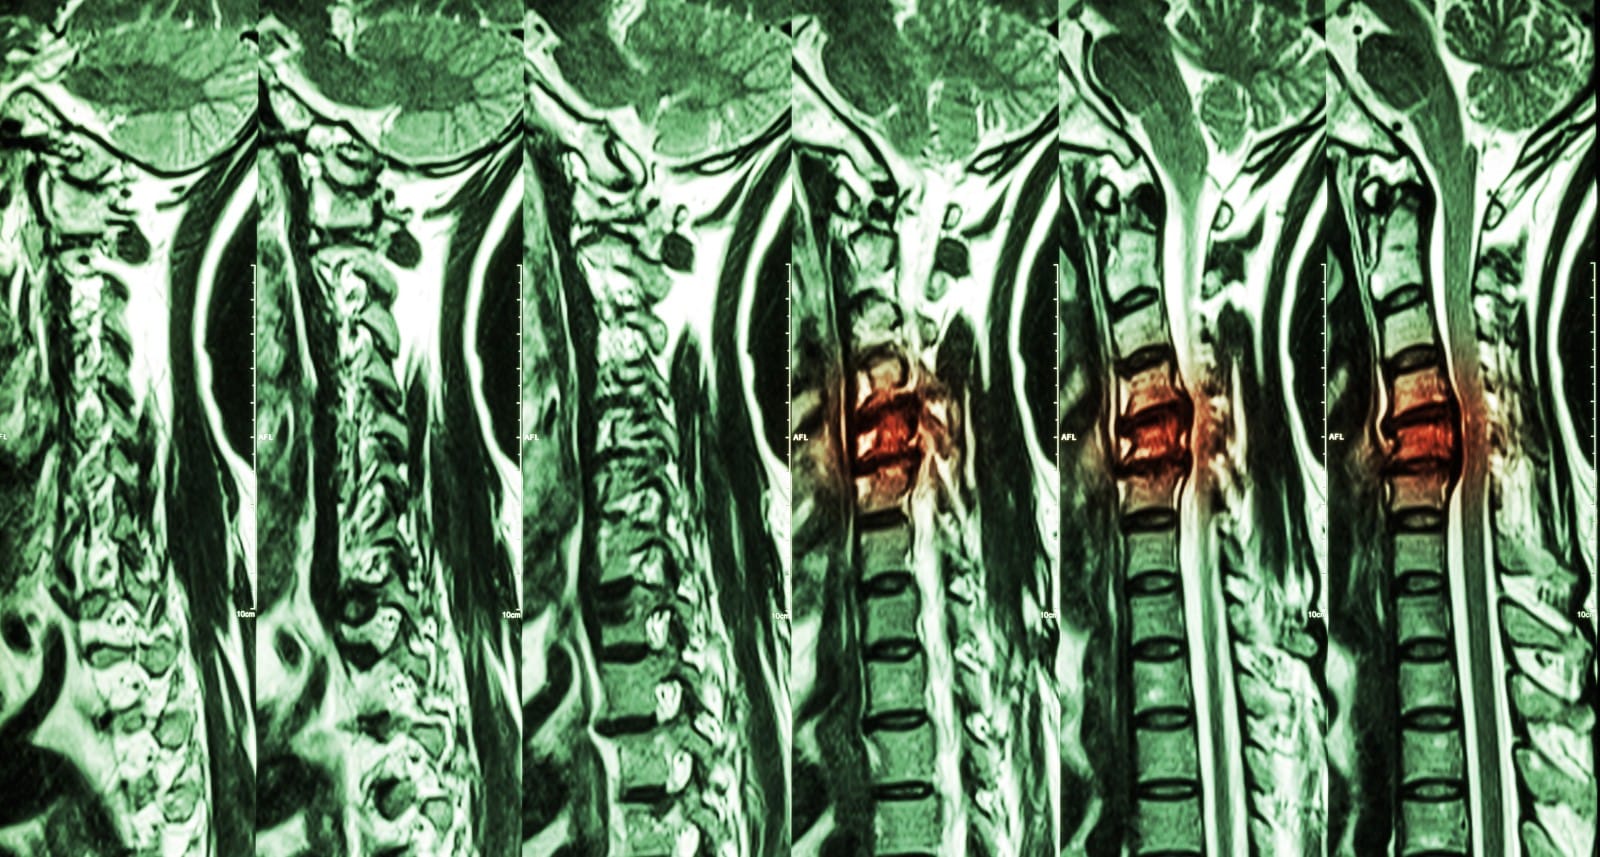

Imaging Of Spinal Cord Compression vrogue.co Spinal Cord Compression After Car Accident spinal stenosis is a condition where the spinal column narrows and puts pressure on the spinal cord and. spinal cord injuries (scis) are complex medical conditions resulting from spinal cord damage, often caused by trauma, as in motor vehicular. a spinal cord injury is damage to the bundle of cells and nerves that carry incoming and outgoing. Spinal Cord Compression After Car Accident.

Spinal cord compression MRI wikidoc Spinal Cord Compression After Car Accident a spinal cord injury is damage to the bundle of cells and nerves that carry incoming and outgoing messages between the brain and the rest of the body. cervical spondylotic myelopathy (csm) is a neck condition that occurs when the spinal cord is compressed due to aging changes in the spine. spinal stenosis is a condition where. Spinal Cord Compression After Car Accident.